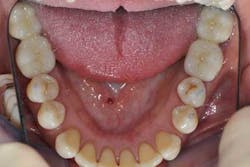

Figs. 8a, b, c, and d: Final results